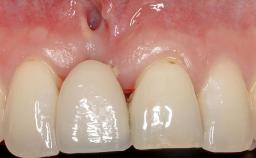

Soft-Tissue Volume Augmentation Using a Connective-Tissue Graft Harvested from the Maxillary Tuberosity

Soft Tissue Grafting Simultaneous